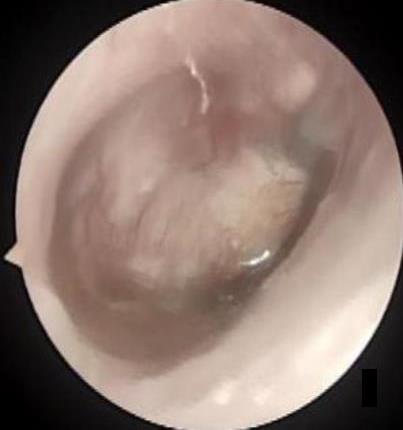

• 医用生物蛋白胶应用于耳内镜下鼓膜修补术的临床疗效

摘要:目的 分析医用生物蛋白胶应用于耳内镜下鼓膜修补术的临床疗效。方法 回顾性分析2022年10月-2023年10月该院收治的60例单纯鼓膜穿孔患者的临床资料,根据手术方法不同,将患者分为研究组和对照组,各30例。研究组术中使用医用生物蛋白胶粘合残余鼓膜和修补材料;对照组术中采用明胶海绵覆盖修补鼓膜。观察两组患者术后的鼓膜愈合情况(鼓膜愈合率、愈合时间、干耳时间和外耳道上下径)和并发症发生情况;于手术前后,采用纯音测听法(500、1 000、2 000、4 000 Hz),测量两组患者气导阈值,观察听力改善程度;采用视觉模拟评分法(VAS)评分,评估患者术后疼痛程度。结果 两组患者术后鼓膜愈合率、愈合时间、外耳道上下径和并发症发生率比较,差异均无统计学意义(P > 0.05)。研究组术后平均气导听阈明显低于对照组,差异有统计学意义(P < 0.05)。研究组术后干耳时间短于对照组,术后第1天疼痛VAS评分明显低于对照组,差异均有统计学意义(P < 0.05)。结论 医用生物蛋白胶应用于耳内镜下鼓膜修补术,可有效地降低气导听阈,缩短干耳时间,减轻患者疼痛,且不增加并发症发生率,值得临床推广应用。